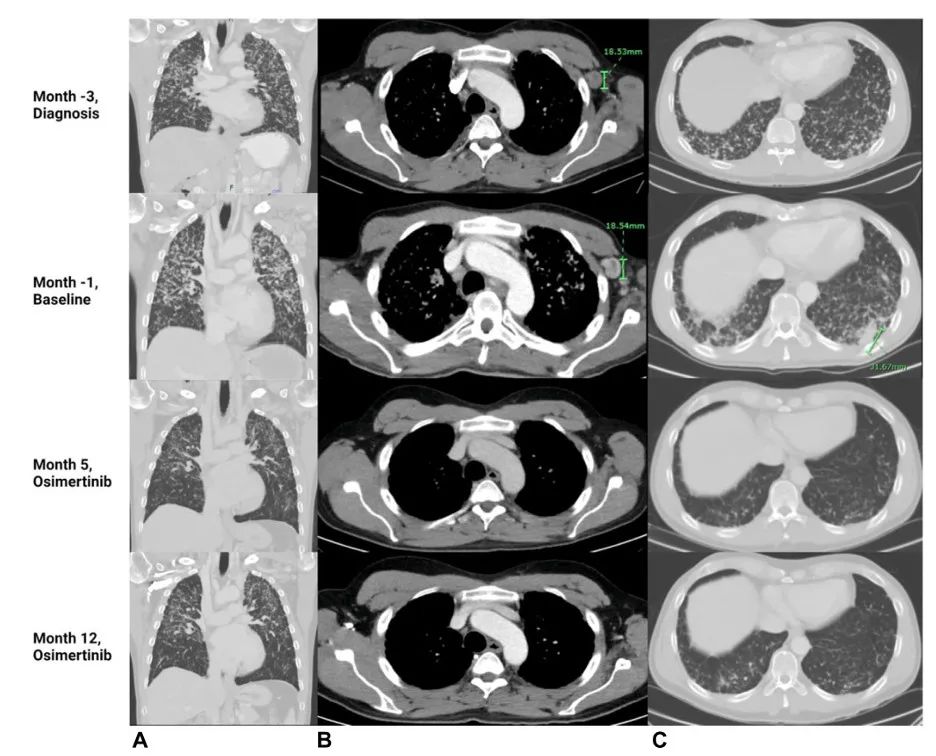

图2.在诊断、基线(化疗+免疫治疗进展时间)、奥希替尼治疗第5个月和奥希替尼治疗第12个月时(A)肺、(B)腋窝淋巴结和(C)肺基底部的CT图像。影像学检查显示疾病(弥漫性实质性肺疾病、左腋窝淋巴结肿大和肺基底部结节)缓解。